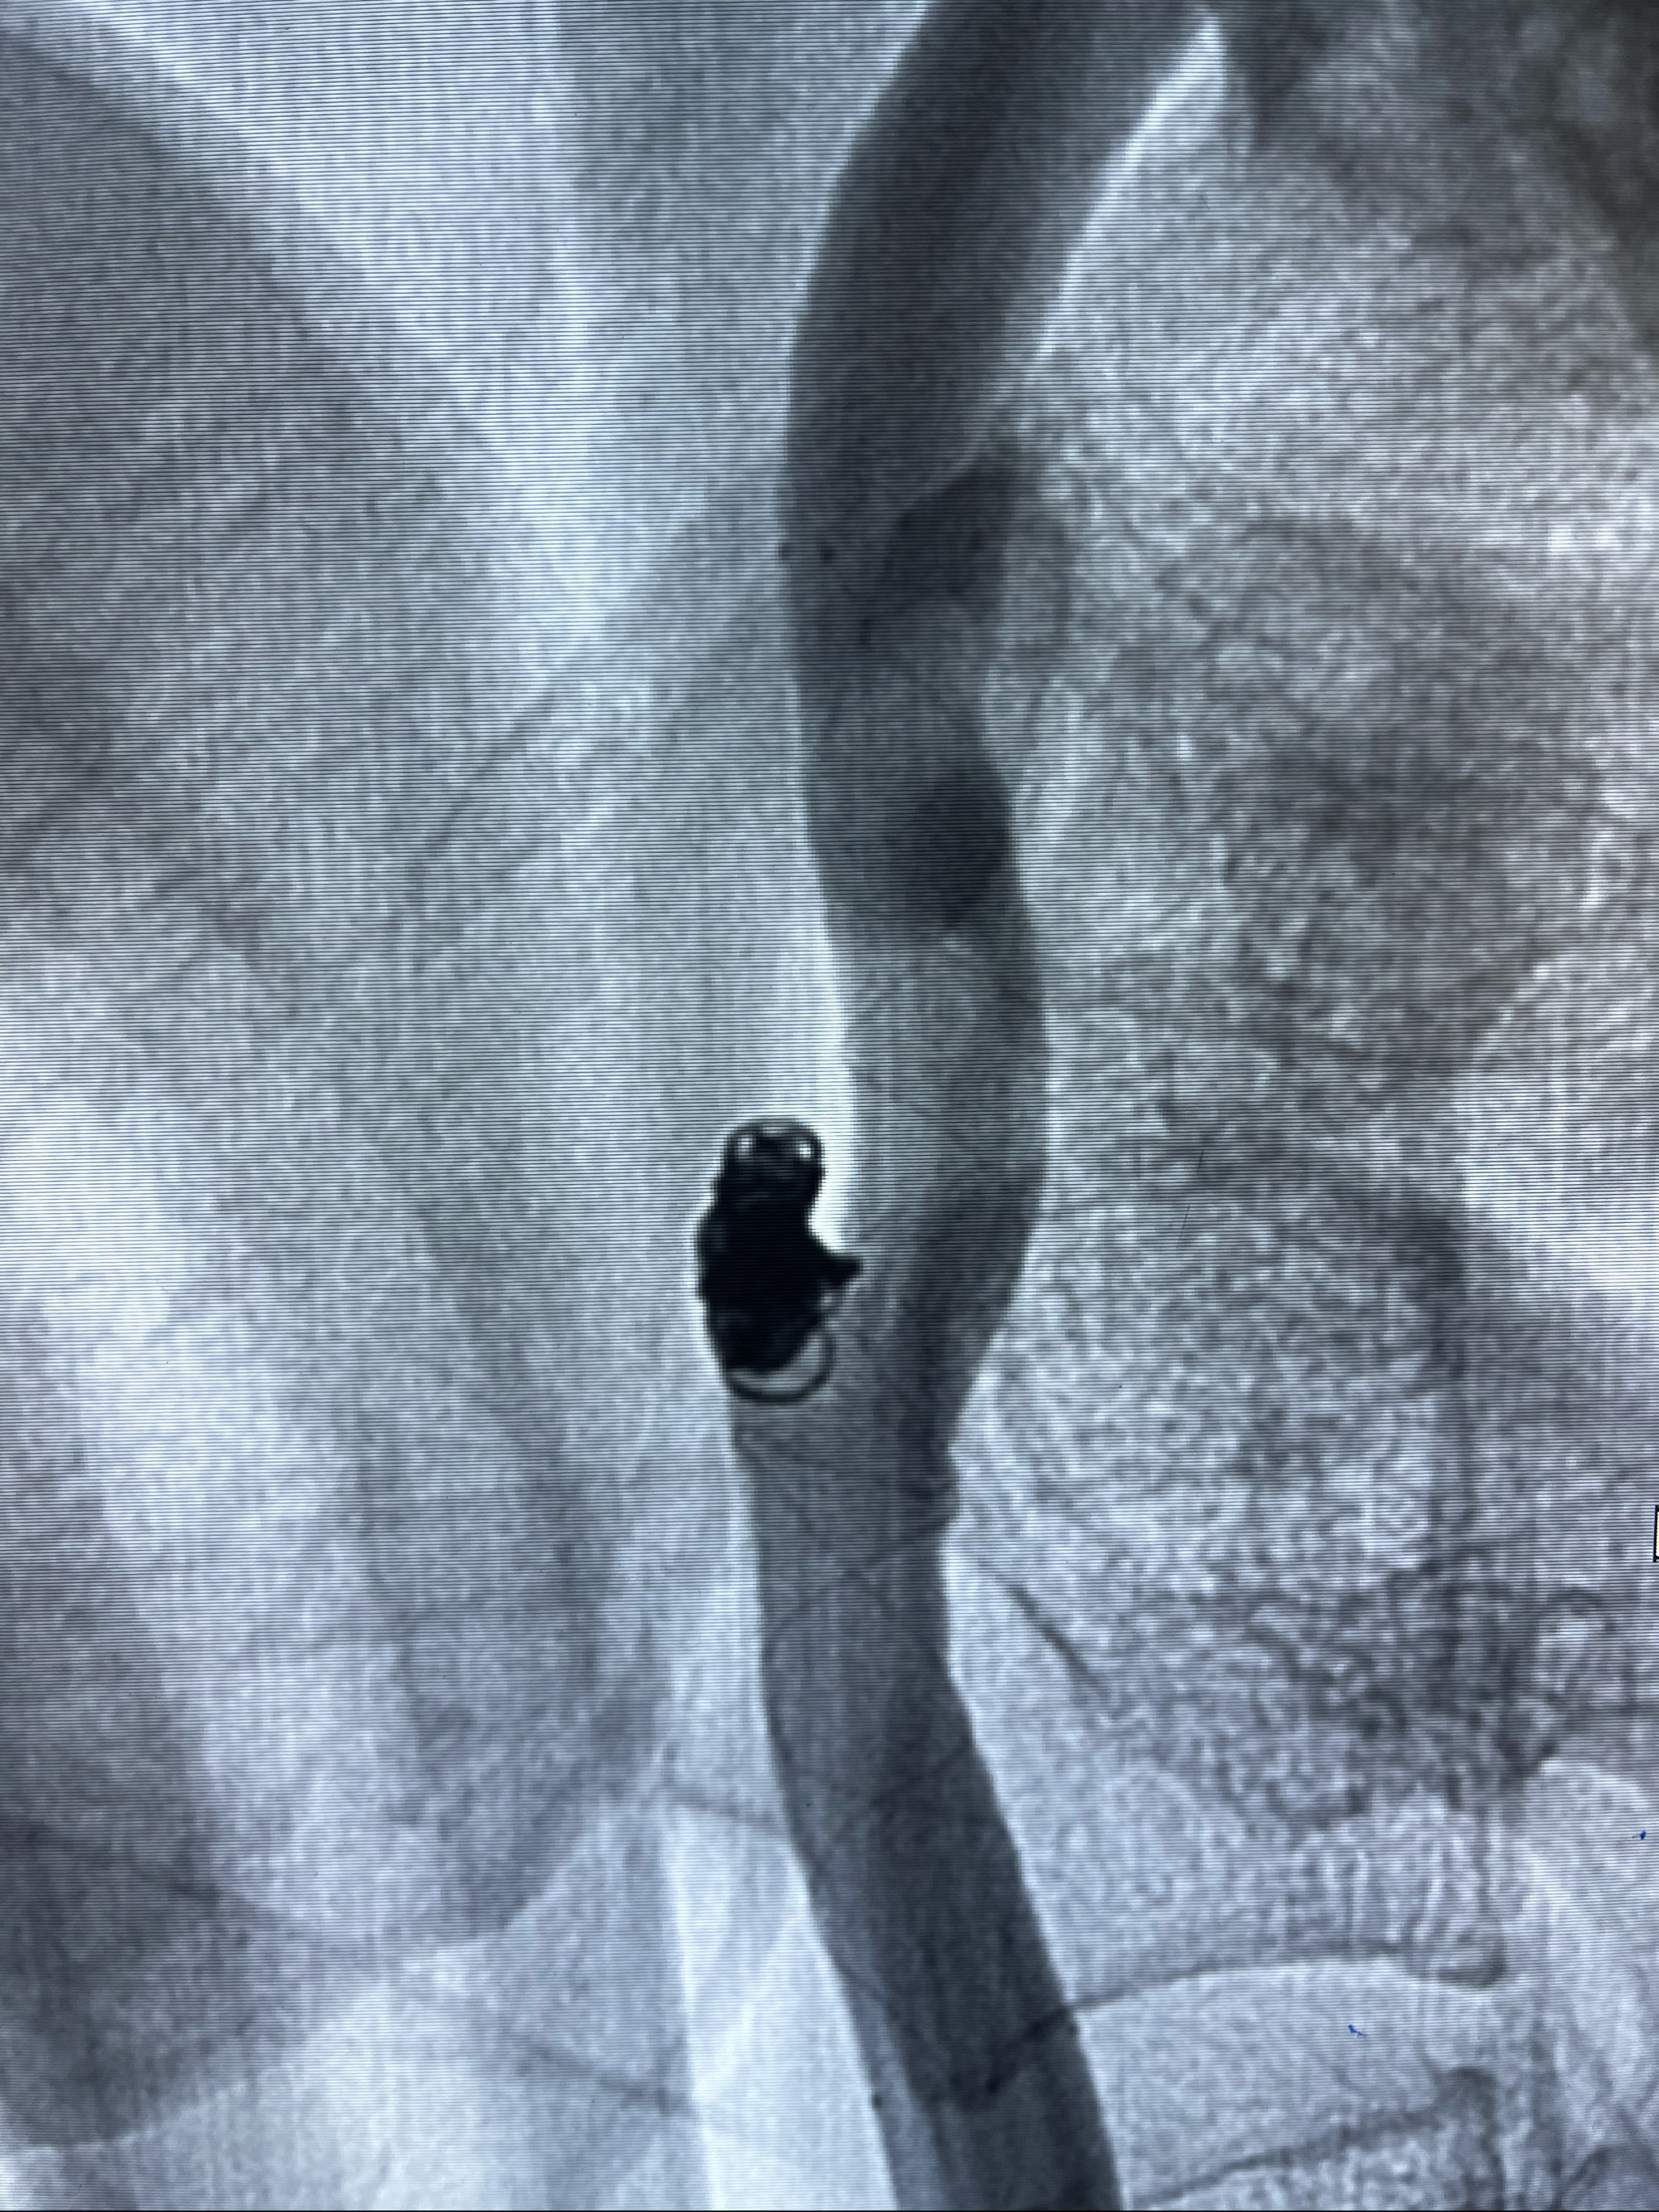

支架到位

支架释放,透视下